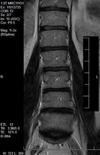

The scans show possibly small bulges at the lower two levels. More important for me are the clinical findings; bulging discs in normal people are common.